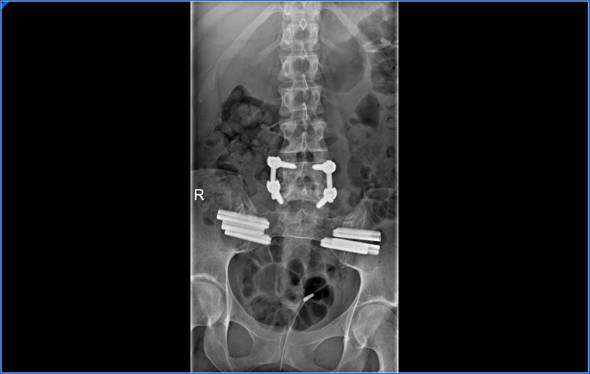

Pero el dolor continuaba y había que entrar de nuevo en quirófano, esta vez eran las articulaciones sacroilíacas, teníamos que fusionarlas, una técnica poco invasiva pero a su vez era una técnica nueva que estaban empezando hacer así que decidimos emprender de nuevo el camino.

La primera artrodesis sacroilíaca la llevé más o menos bien, era la parte derecha, las fijaron con 3 tornillos de titanio y la cosa no es que hubiese mejorado mucho, así que teníamos que hacer la parte izquierda y esa sí que fue dura de verdad, mi pierna izquierda no es la más fuerte, es la del pié equino y siempre me había dado muchos problemas, musculatura atrofiada, psoas, isquiotibial, piramidal, esos músculos que parecen sacados de un partido de fútbol estaban dando demasiada guerra y desesperación por todas partes. Que más se podía hacer?; Si ,hay que fijar la vértebra que queda suelta pero…necesito estar 100% en todo para poder pasar por ahí, no solo físicamente sino moralmente.